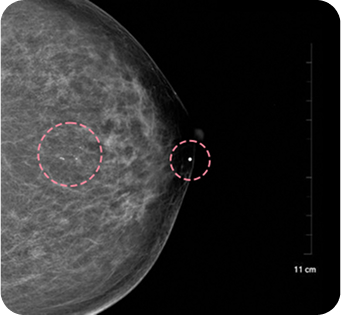

맘모톰시술 후 병리조직검사 결과 상피내암(조기 유방암)

초기로

진단되어 항암치료 없이 간단한 수술로 치료가

가능했습니다. 눈에

잘 띄지 않는 작은 병변까지 확인할 수 있었던 건,

맘모톰의 정밀한

조직검사 기능과 전문의의 정확한 판독이 있었기 때문입니다.